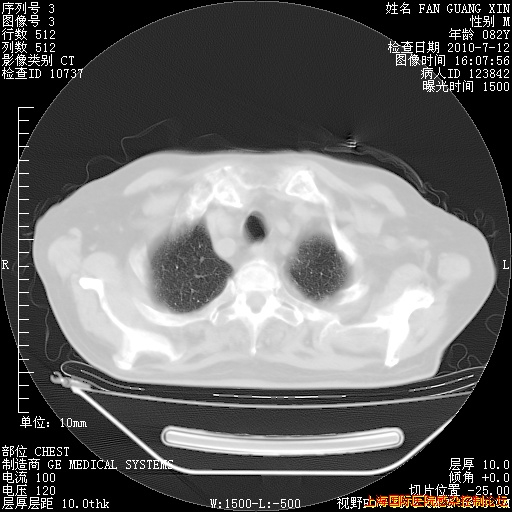

补发6月12日肺部CT肺窗

6月12日肺窗